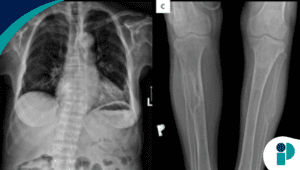

La ivermectina es un antiparasitario aprobado por la Administración de Alimentos y Medicamentos de EE.UU. (FDA) para tratar infecciones específicas en humanos. En su presentación en tabletas, está indicada para combatir la estrongiloidiasis intestinal y la oncocercosis, también conocida como ceguera de los ríos. La estrongiloidiasis es causada por un gusano que puede reproducirse en pulmones e intestinos, arriesgando seriamente la salud de personas inmunocomprometidas. Por su parte, la oncocercosis, transmitida por moscas negras infectadas, puede migrar hacia órganos internos como los ojos y es una de las principales causas infecciosas de ceguera en el mundo.

Además de su uso oral, la ivermectina también se utiliza tópicamente en crema para tratar afecciones como los piojos y la rosácea.